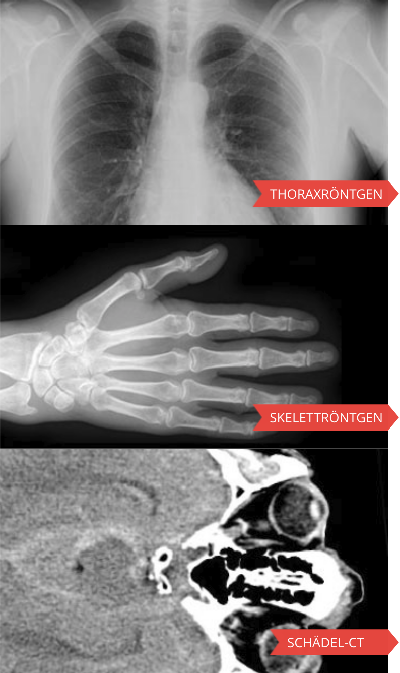

Radiosurf